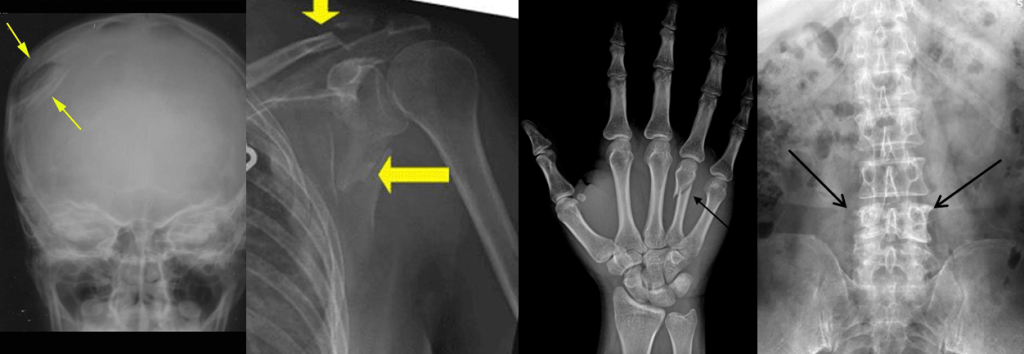

Modern AI systems are often described as “narrow”, meaning they are usually very good at performing a single, often binary, classification task. For example, deciding if a bone is fractured or not. This is fairly simple task, there is a limited set of features that we need to look for, and a fairly consistent type of input image. But even then, we can see that this task is made up of a variety of subtasks and features.

For example, fractures can have different shapes.

Fractures can have different radiographic features.

They can occur in different body parts.

So with all of this variation … is it really a single, narrow task? Can a model even learn to detect fractures, or does it really learn to detect a variety of patterns, involving different combinations of visual features in different sets of images?

We can see that narrowness is not a clearly defined thing, where some models are narrow and some are general. Rather, narrowness is a spectrum. A fracture detector which only looks for displaced skull fractures is far more narrow than a system that is intended to detect any fracture, particularly fractures with visually distinct features such as undisplaced radial head fractures (see the “joint effusion” picture above, the only evidence of the fractured bone isn’t even in the bones, it is a change in the soft tissues).